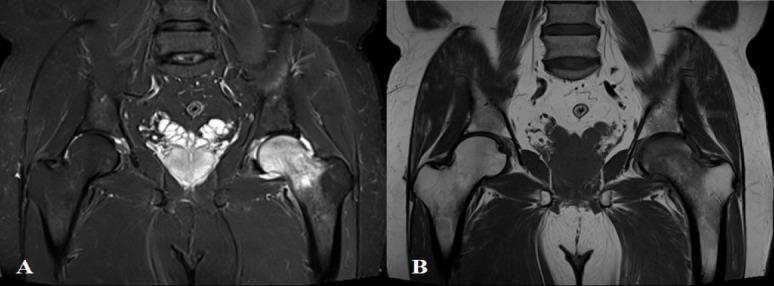

We retrospectively collected the data of patients who were diagnosed with TOH from March 2017 to March 2022. A total of 10 patients with a mean age of 43.7 years (range 33-56 years) were included in the study. The mean time to presentation from the onset of symptoms was 4 weeks (range 2-8 weeks) Radiologic evaluation with radiographs was sensitive in only 8 patients with osteopenia, whereas magnetic resonance imaging (MRI) was sensitive in all the patients and aided in early diagnosis of TOH. Radiographic evaluation alone leads to a mean delay in TTD of 1.6 weeks (range 0-8 weeks) in our study. All the patients were treated conservatively without any major complications.

我们回顾性收集了2017年3月至2022年3月期间被诊断为TOH的患者数据。共有10名患者纳入研究,平均年龄43.7岁(范围33 - 56岁)。从症状出现到就诊的平均时间为4周(范围2 - 8周)。X线平片的放射学评估仅对8名骨质减少患者敏感,而磁共振成像(MRI)对所有患者均敏感,有助于TOH的早期诊断。在我们的研究中,仅进行X线平片评估导致诊断时间平均延迟1.6周(范围0 - 8周)。所有患者均接受保守治疗,无任何重大并发症。